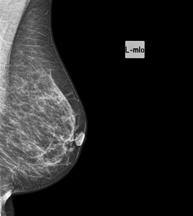

Mammography

Mammography tests use low-dose x-ray imaging to detect breast tissue pathologies (especially breast cancer) in gynaecological screening and targeted diagnostics. Mammography can be interventional with cyst puncture, stereotactic biopsy, pre-surgical marking, and galactography.

Digital mammography

Digital mammography is an innovative breast examination technique that uses a low radiation dose, thus reducing exposure compared to conventional mammography. The image is digitised using special cassettes on a system known as CR (Computed Radiography). These digitalisation techniques provide excellent images, especially in breasts that are difficult to examine, such as glandular breasts, which appear dense on mammograms, enabling better detection of tumours in this group of patients.